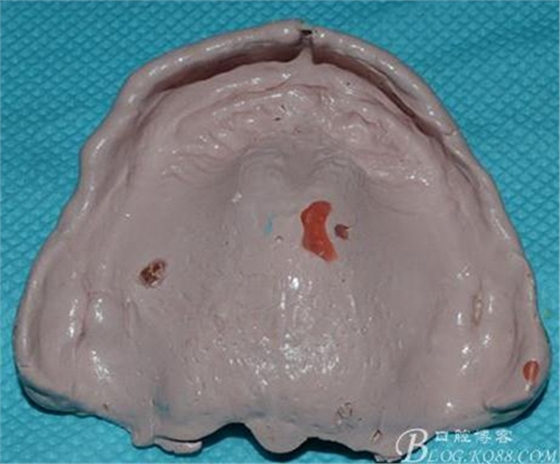

上圖是某一廠家的輕體終印

下圖是另一廠家的,具有更好流動(dòng)性和親水表現(xiàn)的超清體。

印模取出來(lái)有兩個(gè)大氣泡和幾個(gè)小氣泡。。。但是!組織面的細(xì)節(jié)啊。。。邊緣那個(gè)細(xì)膩完美啊。。。

請(qǐng)無(wú)視略過(guò),注意力細(xì)節(jié)表現(xiàn)~~~

簡(jiǎn)易圍模后完成的最終模型: